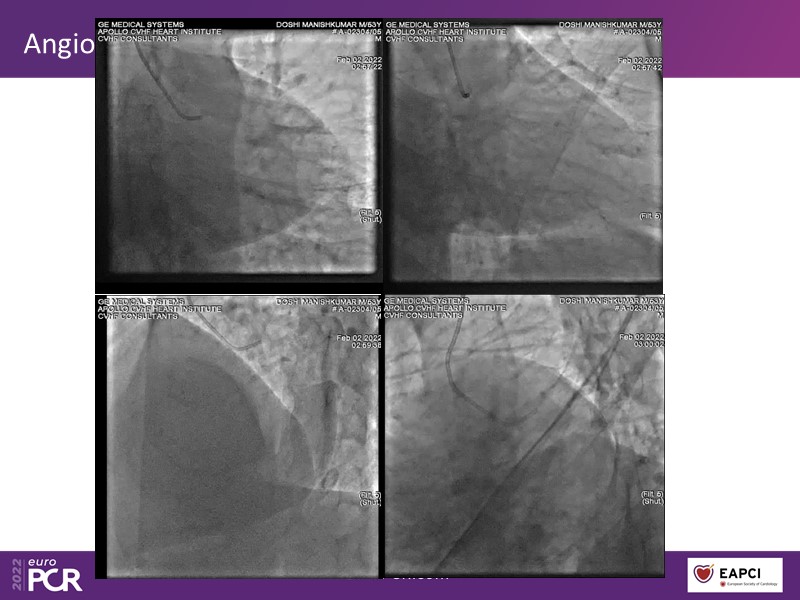

- To know why sirolimus coated balloon is the ideal choice in native vessel disease treatment through a case presentation